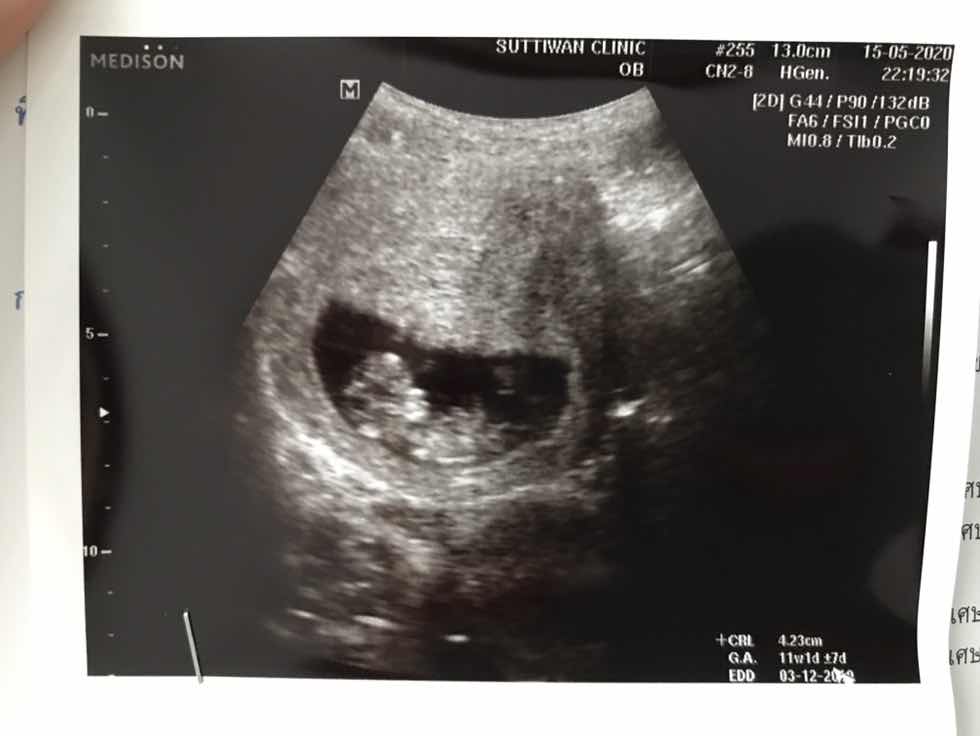

ขอดูใบซาวหน่อยจ้า เเล้วกำหนดคลอดวันที่เท่าไรกันค่ะ

3 ธ.ค. 🥰